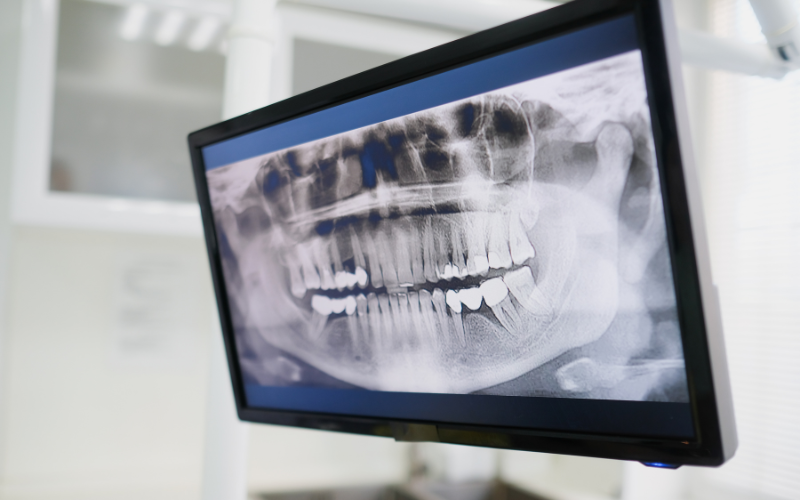

One of the most exciting advancements in modern dentistry is the use of digital technology. With digital dentistry, dentists can now design and simulate a patient’s future smile before any treatment even begins. Using digital scanning, 3D imaging, and computer-assisted design systems, dentists can analyze the patient’s teeth, bite, and facial proportions with exceptional accuracy.

Digital tools also make procedures faster, safer, and more comfortable. Traditional messy dental impressions are increasingly replaced by digital scans, and restorations such as veneers or crowns can be designed with remarkable precision.